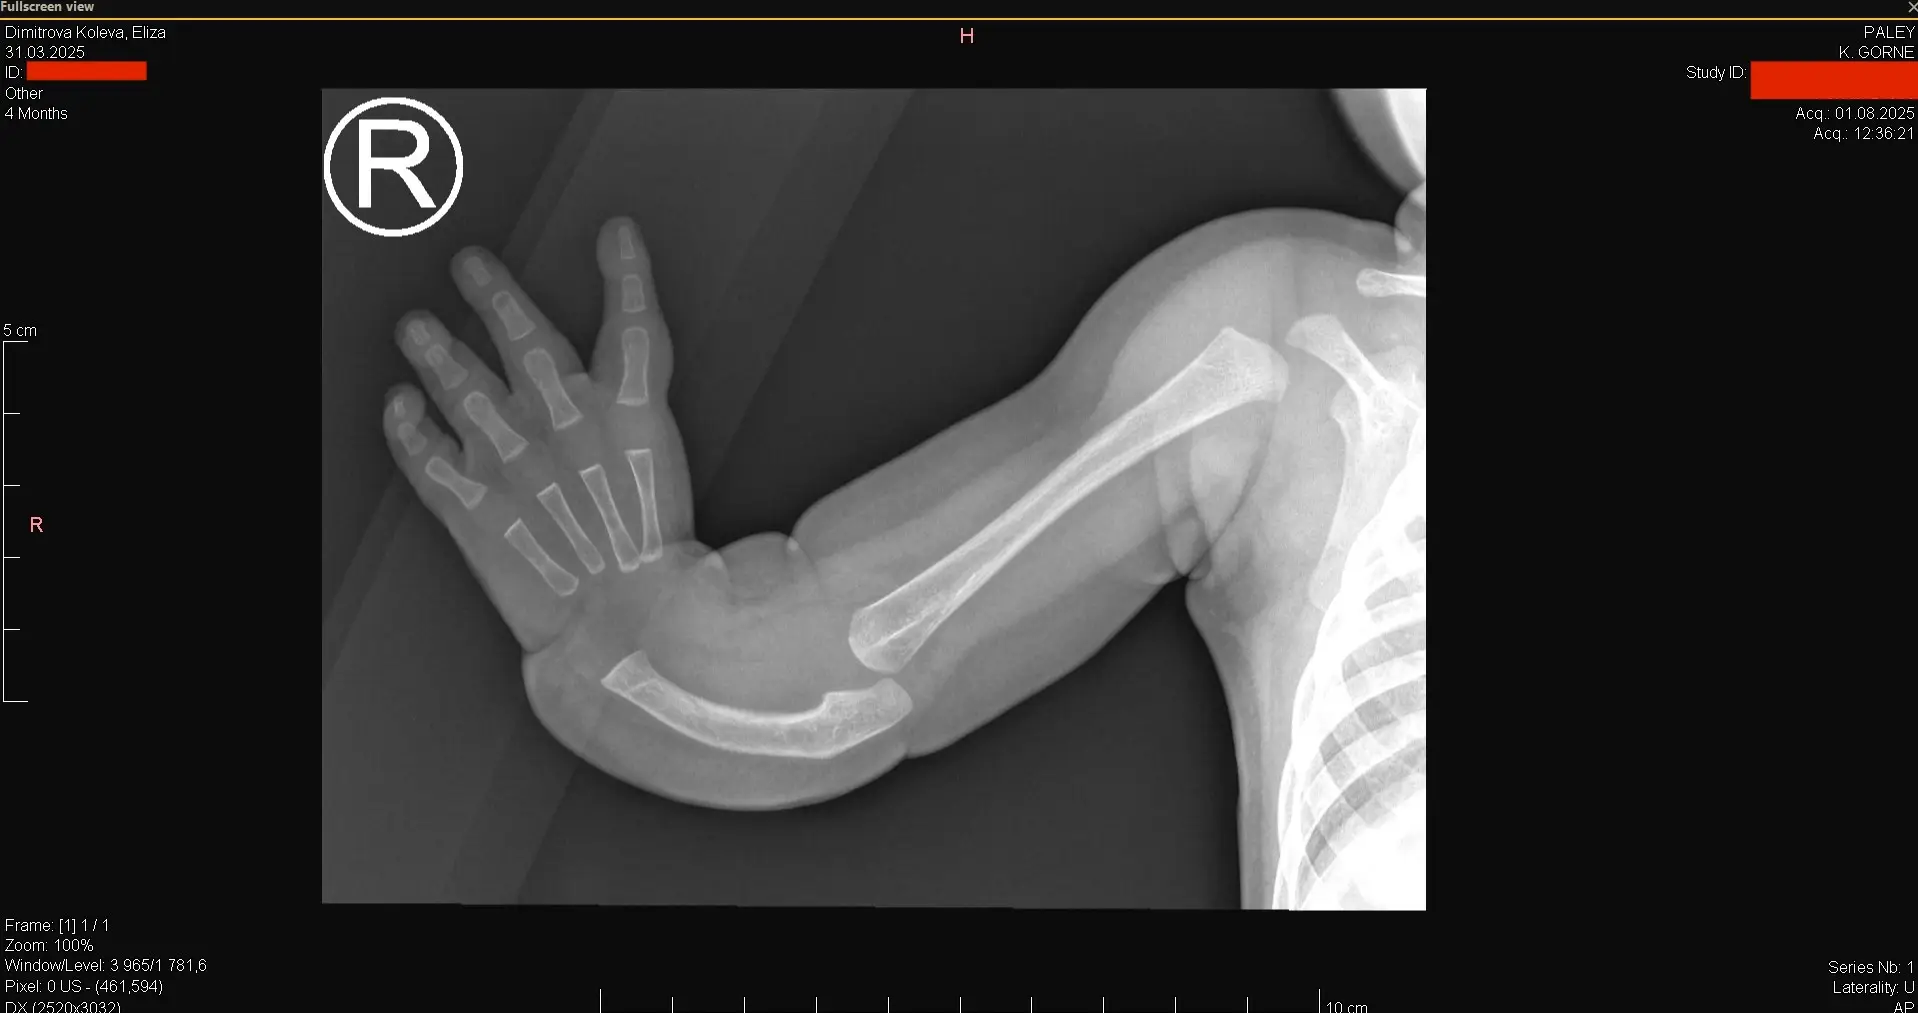

След като се възстанови успешно през лятото, дойде време да се заемем и със следващия проблем - много рядка аномалия на дясната ръка - т.нар “Club Hand” или вродена липса на радиална кост и палец.

При направена консултация с водещия световен хирург-ортопед Др. Пейли, в Полша през август 2025, бе изготвен следният план за лечение, включващ 2 операции на ръката:

Първата операция ще се извърши след навършване на 18 месечна възраст и включва улнаризация - преместване на костите на ръката и китката от страната на малкия пръст с хирургичен разрез и дорзално преместване на сухожилието (FCU) за стабилност със скъсяване на улната кост, за да се създаде здрава и стабилна става. Необходимо е да се поставят фиксатори за временна артродеза на китката. Под същата анестезия се оперира и палеца на лявата ръка, поради нестабилност на улнарния колатерален лигамент, като се прави реконструкция на UCL и остеотомия на първия метакарпал с разширяване на междупръстното пространство.

Втората операция е три месеца по-късно и включва отстраняване на външните и вътрешните фиксатори на дясната китка и изместване на показалеца, който ще служи за палец - т.нар полисизация.